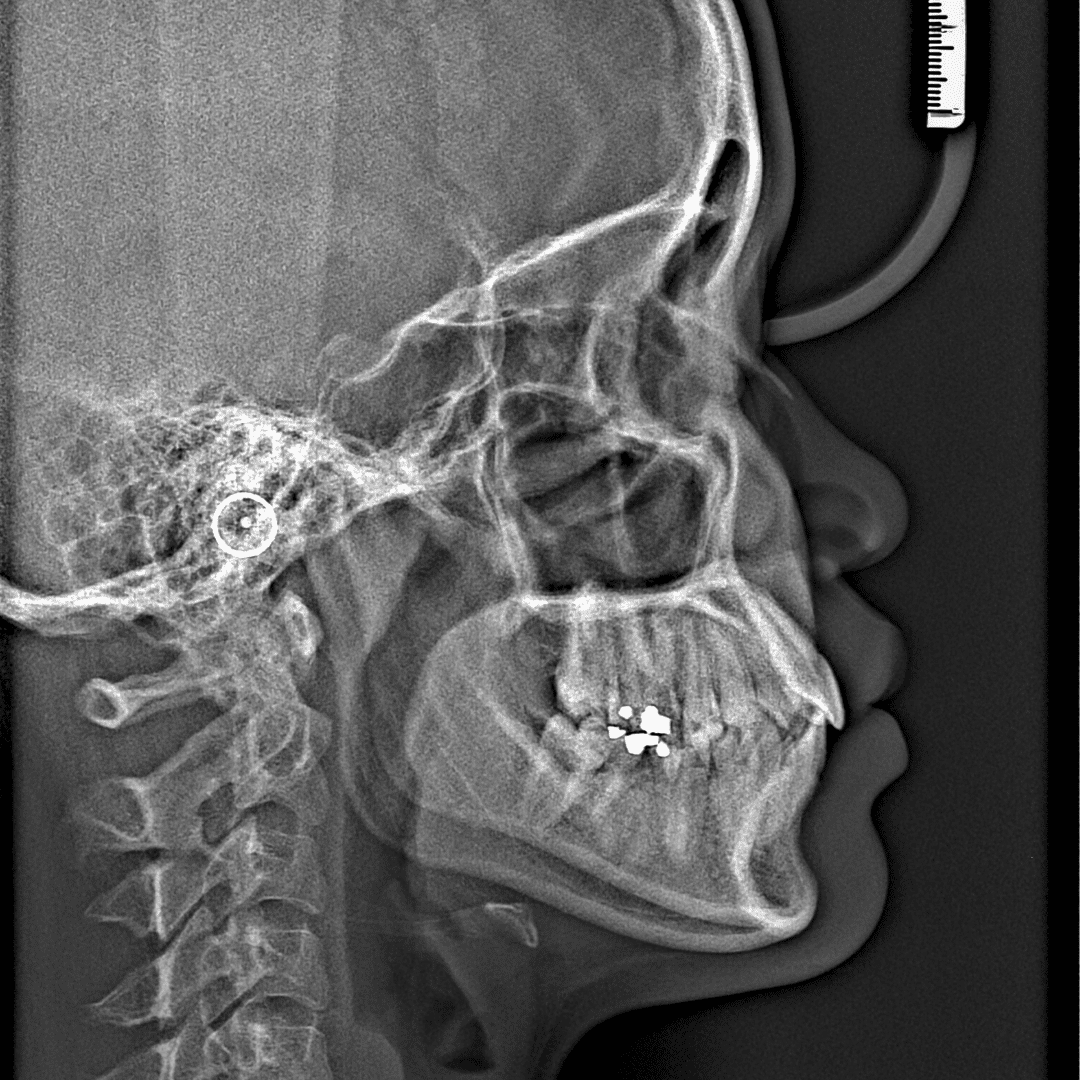

Advanced Digital Care at Dr Osman Akıncı Clinic Temporomandibular joint disorders (TMJ / TMD) are complex conditions that often require